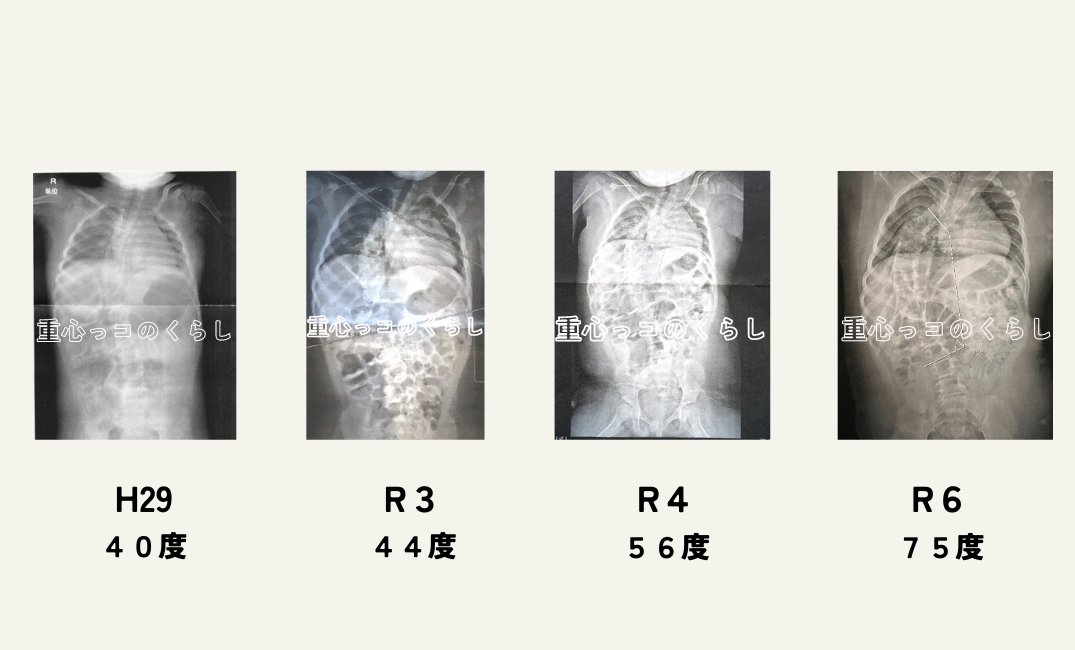

両下肢と左上半身に麻痺があり、三肢麻痺と診断されています。その影響で、1才の頃にはすでに側弯の症状が出ていました。赤ちゃんの頃から半年おきに整形外科で経過観察をしてもらっており1歳で既に側弯の角度は30度、小学生に入る頃には40度。

側弯と診断された時点で、思春期は要注意だと言われていて、小学2年生ごろまではボトックス注射を1年に一度打ち、幼児期からプレーリーという体幹装具も作成し学校やリハビリで使用していました。しかし、本人が装具をつけることや注射を拒否したため、なかなか側弯への対応が出来なくなり、現在はなんとかリハビリの時に装具を付けれる程度になってしまっています。

側弯の経過

小学校高学年になり思春期を迎え、体重も増加してしまい急激に側弯が進行しました。現在側弯は75度、体の成長に伴い急激に進んでしまいました。

側弯については、現在も半年に一度の経過観察を行なっている状態です。今後も、こちらのホームページの方で経過を報告していきたいと思っています。